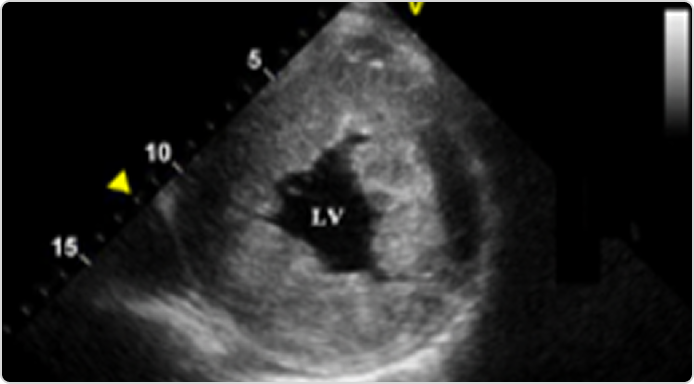

ЭхоКГ

• СҚ еркін қабырғасының гипертрофиясы13,15

• СҚ-ның концентрлік гипертрофиясы (13–22 мм)12,15,17

• митральді қақпақша жармаларының қалыңдауы12-14

Фабри ауруы кезіндегі сол жақ қарыншаның эхокардиографиясы

1-сурет.

Парастерналды эхокардиография: ұзын (A) және қысқа (B) біліктер.

Дереккөзден бейімделген:

Liu et al., PLoS One 2013;8(5):e64603.

CC BY 4.0.18

Эхо-КГ-да сол жақ қарыншаның концентрлік гипертрофиясын көрсету

(датчиктің парастерналды орналасуындағы қысқа ось проекциясы)